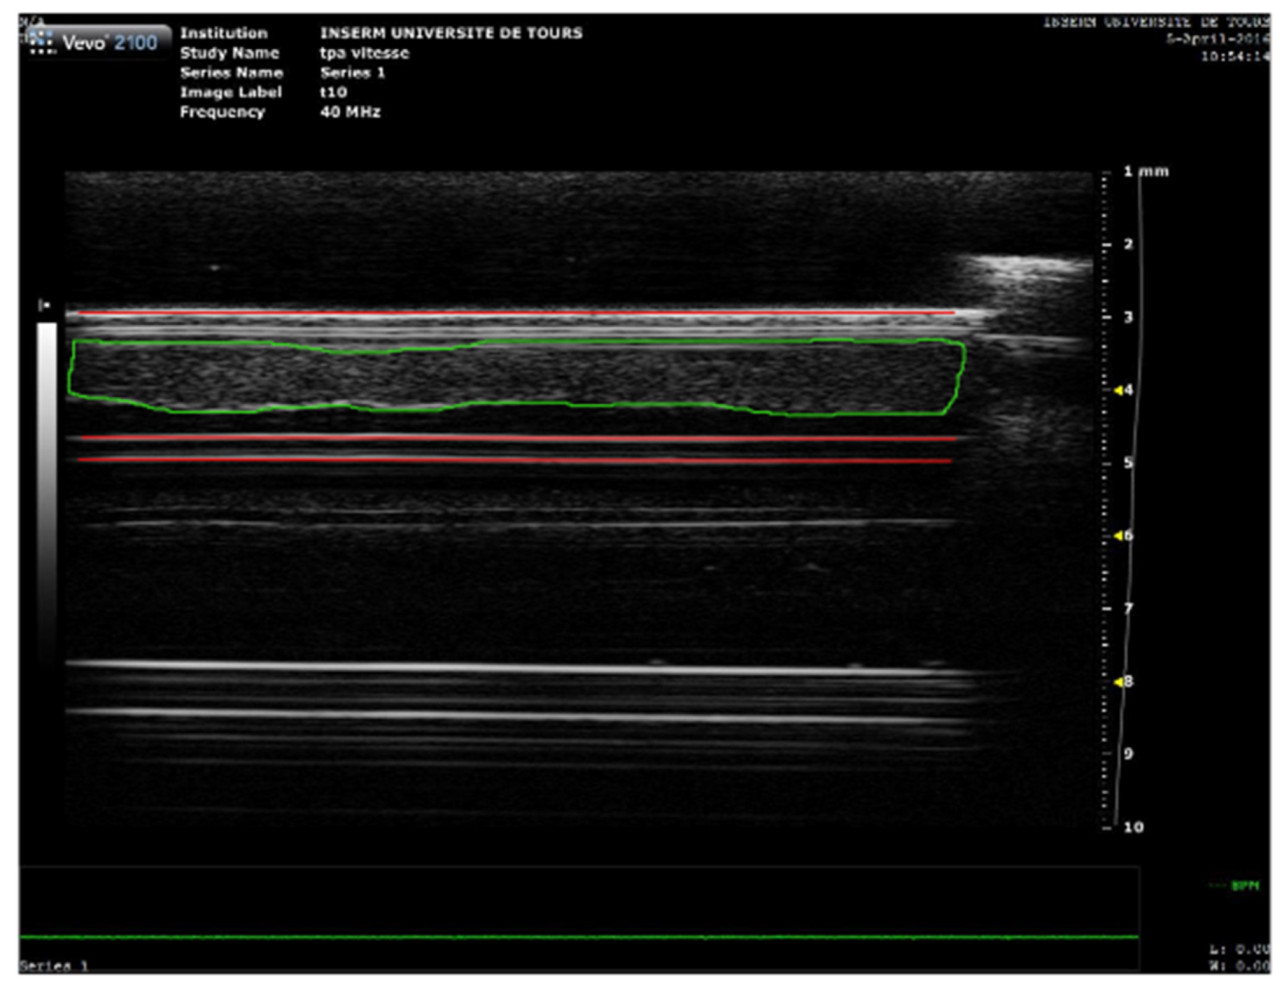

2.5. High Frequency Ultrasound Imaging and SoS Measurement

A Vevo® 2100 ultrasound scanner (VisualSonics Inc., Toronto, ON, Canada) with an MS-550D probe (22–55 MHz; 40 µm axial and 90 µm lateral resolutions) was used to acquire blood clot images every 1 min for 30 min (Figure 1). After acquisition, the images were analyzed using a custom MATLAB® code to calculate the SoS, i.e., longitudinal wave, inside the blood clot. As depicted in Figure 2, the front and bottom of the tube were semi automatically delineated as well as the thickness of the clot in echographic images acquired with the Vevo® 2100 ultrasound scanner. The distance between the 2 walls was first measured when water filled the tube. The distance was then measured when plasma filled the tube to estimate the SoS in plasma. Then, this distance was measured with the clot during the experiment every minute. The SoS in the clot was deduced by reporting the difference of SoS with and without the clot to the thickness of the clot.

Figure 2.

High frequency ultrasound imaging of blood clot. A 2D image of the blood clot obtained with the Vevo 2100®. The red lines delineate the anterior and the posterior walls of the tube, while the green shape delineates the clot.